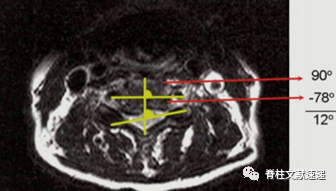

图注:脊髓相对于椎体的旋。

分为三型:1型为轻度旋转(0°- 5°),2型为中度旋转(6°- 10°),3型为重度旋转(≥11°);

脊髓旋转是术后C5神经根麻痹的一个显著的预测因素;

脊髓旋转程度越大,患者术后发生C5神经麻痹的风险越大。